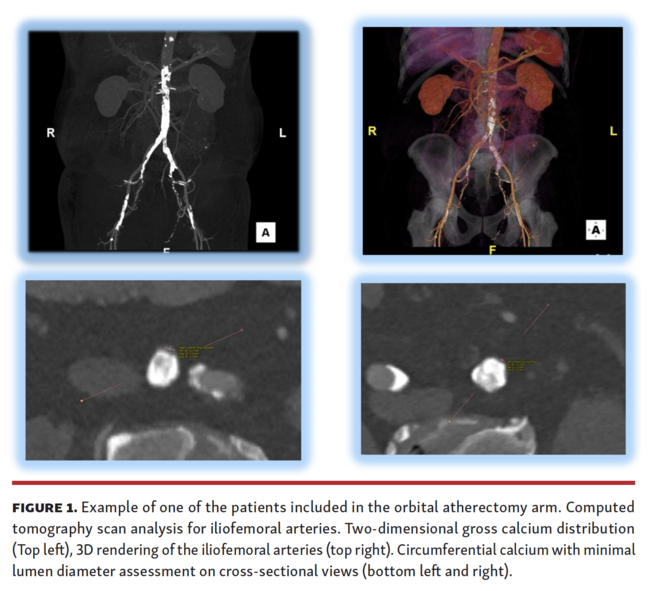

CT review. All CT scans were analyzed using a dedicated workstation (3Mensio Valves Software, Pie Medical Imaging) at the interventional site from the common femoral artery (CFA) to the distal aorta. The following measurements were obtained: minimal lumen diameter (MLD); maximum luminal diameter; vessel area at the site of the most severe narrowing; degree of vessel calcification; and tortuosity. The mean lumen diameter was computed as the average vessel diameter (maximal + minimal diameter/2), measured at the MLD. Calcification was defined as severe if an arch >270° was present (Figure 1).